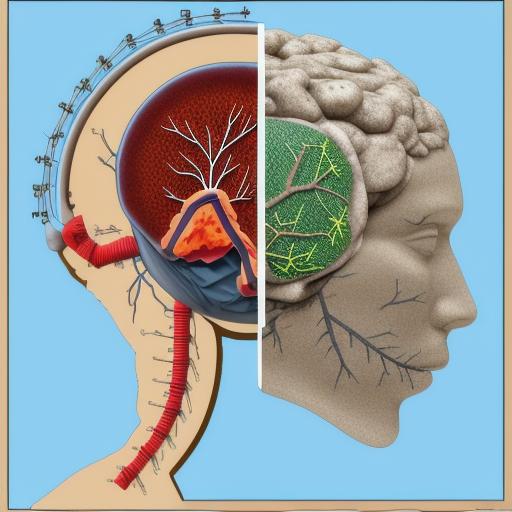

Cognition,List of political entities in the 2nd century,Harbor , as a trash figure

List of state leaders in the 2nd century,Cabinetry,Kidney , as a trash figure